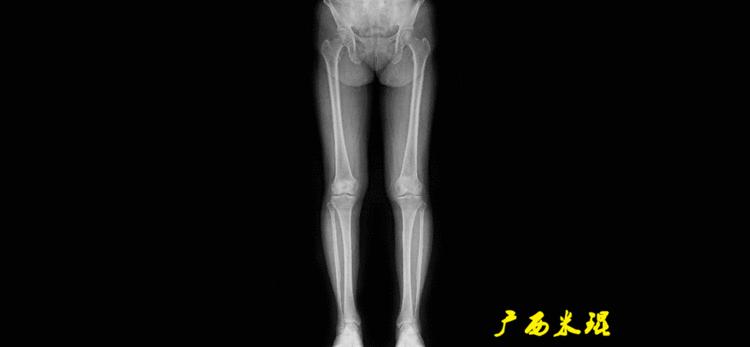

下肢力线及相关角度测量的前提是必须拍摄标准的站立位也就是负重位的下肢全长片。目前这样的照片都是放射科的技师在电脑上拼接出来的,大部分医院的DR都能够做到这一点。

无论如何,拍摄出来的下肢全长片必须包含髋关节中心、膝关节中心及踝关节中心,否则对临床是无用的。有了一张下肢的全长照片,我们需要确定下肢关节的中心点,通过中心点画出下肢的各种轴线,然后利用轴线与关节线的相交得出各种所需要的角度。

机械轴要分前后位及侧位,站立前后位(也就是冠状面)股骨头中心与踝关节中心的连线通过膝关节中心,这是下肢的机械轴线,也就是下肢力线,常说Mikulicz线。冠状面的力线评估在临床工作中最常用、最基础、最重要。

最常见的下肢畸形发生于冠状面,即膝内外翻畸形,冠状面的对线异常通过应用“对线异常检验”进行分析,机械轴的偏移(MAD)表现为对线异常。

膝内翻是指下肢力线通过膝关节中心点内侧,距中点2mm以上,偏内超过15mm为显著膝内翻。膝外翻是指下肢力线通过膝关节中心点外侧,距中点2mm以上,偏外超过10mm为显著膝外翻。